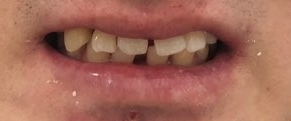

다시 원래 상태와 비교해 볼까요?

원래상태

여기에서 아래 사진처럼!!

윗니를 비교해주세요! (아랫니는 안건드렸어요)

원래보다 훨 좋아지셨죠!!